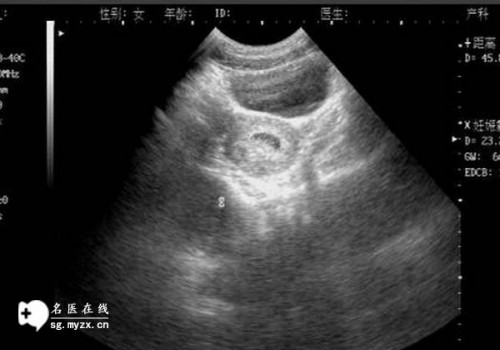

輸卵管堵塞是一種關(guān)于生殖健康的常見問題,因為它可能影響到生育能力。輸卵管堵塞可能會導(dǎo)致不孕不育。因此了解輸卵管堵塞的原因和預(yù)防措施,以及如何處理它們,是非常重要的。

輸卵管堵塞的原因可以分為內(nèi)部原因和外部原因。內(nèi)部原因是指輸卵管的結(jié)構(gòu)本身導(dǎo)致的,比如輸卵管的萎縮、內(nèi)膜發(fā)育不良、輸卵管結(jié)石等,都可能導(dǎo)致輸卵管堵塞。外部原因一般是指外部因素導(dǎo)致的,比如宮外孕、宮腔粘連、外傷等,這些都可能會導(dǎo)致輸卵管堵塞。

輸卵管堵塞的癥狀一般比較模糊,常見的癥狀有疼痛、反復(fù)發(fā)熱、反復(fù)腹痛和經(jīng)期不規(guī)律等,這些癥狀可能會讓人感到困擾。

當(dāng)發(fā)現(xiàn)輸卵管堵塞時,應(yīng)及早就醫(yī),并根據(jù)病情選擇適當(dāng)?shù)闹委煼椒āMǔG闆r下,醫(yī)生會根據(jù)患者的具體情況,采用手術(shù)、藥物或血液療法來治療輸卵管堵塞。有時醫(yī)生會采用體外受精的方法來解決輸卵管堵塞問題,以便讓患者成功懷孕。